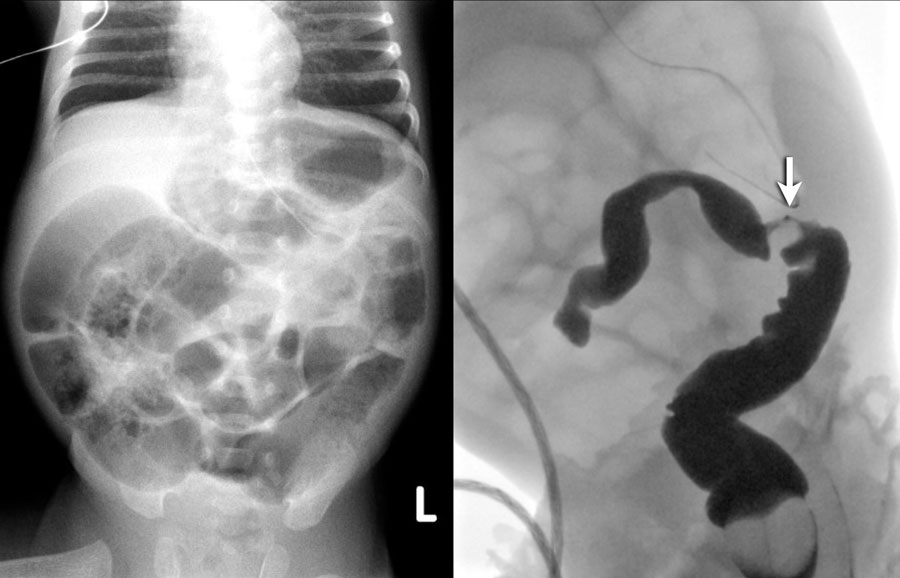

При поражении прямой и сигмовидной кишки визуальный осмотр стенок нижних отделов кишечника с помощью ректороманоскопии дает точное представление о наличии и выраженности болезни. Если язвенный процесс затрагивает вышележащие отделы кишечника, дополнительно могут быть назначены колоноскопия, рентгенография кишечника с контрастированием, МРТ на современном томографе.

Основным диагностическим методом, выявляющим язвенный колит, является колоноскопия, позволяющая детально исследовать просвет толстого кишечника и его внутренние стенки.Ирригоскопия рентгенологическое исследование с барием позволяет обнаружить язвенные дефекты стенок, изменения размеров кишечника (мегаколон), нарушение перистальтики, сужение просвета. Эффективным методом визуализации кишечника является компьютерная томография.